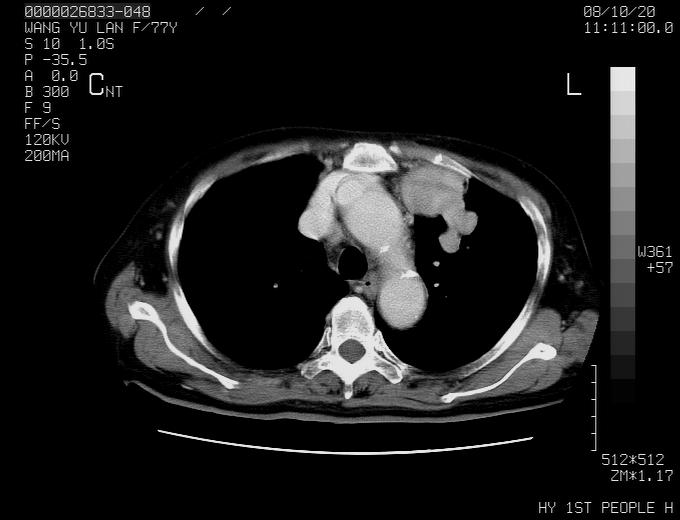

女性,77岁,胸部疼痛半月。左上肺团块影,本人考虑血管畸形,请分析

纵隔有多个淋巴结肿大,提示周围型肺癌并转移可能性大。

动脉期未见大血管同步强化,首先考虑周围型肺癌

动脉期病灶近中线侧可见星芒状与大血管同等强化密度,支持考虑血管畸形伴血栓形成,动脉期不曲型,不除外周围型肺癌

左肺周围型肺癌并肺门淋巴结转移,很典型了!